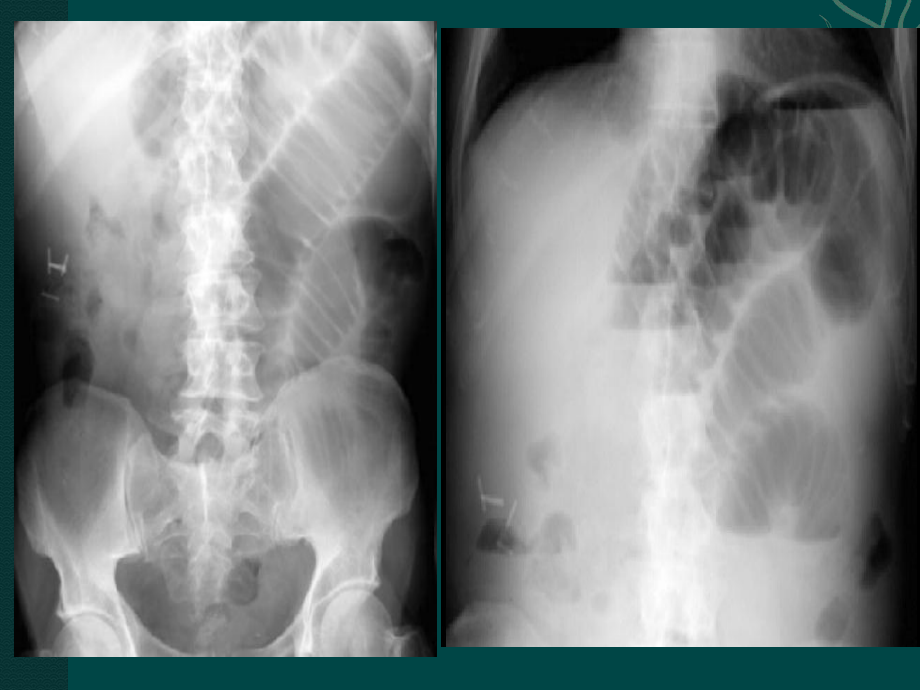

1、病例病例2:男,男,60岁,胆囊切除术后岁,胆囊切除术后12年,年,腹痛、腹胀、肛门停止排气排便腹痛、腹胀、肛门停止排气排便5天。天。问题问题1:临床印象诊断考虑什么?临床印象诊断考虑什么? 患者出现了患者出现了腹痛、腹胀、肛门停止排气排便腹痛、腹胀、肛门停止排气排便5天天的症状,而且有的症状,而且有胆囊切除术后胆囊切除术后12年年的病史,胆囊切除的手的病史,胆囊切除的手术可能会导致肠壁的粘连,梗阻。综合考虑印象诊断为术可能会导致肠壁的粘连,梗阻。综合考虑印象诊断为肠梗肠梗阻阻。 该该做哪些检查?做哪些检查?X线平片(立位和侧位、仰卧位)、造影检查、超声、线平片(立位和侧位、仰卧位)、造影检查

2、、超声、CT首选影像检查方法是什么?首选影像检查方法是什么?X线平片线平片问题问题2:腹部立卧位片可看见哪些腹部立卧位片可看见哪些X线征线征象象? 立位片:可见左上腹,高立位片:可见左上腹,高低不低不等的阶梯等的阶梯状液气平面气体较少,液平大小和肠管状液气平面气体较少,液平大小和肠管大小相近。梗阻远端可见充气影。大小相近。梗阻远端可见充气影。 卧位卧位片:可见空肠积气,较多的环形皱襞影。片:可见空肠积气,较多的环形皱襞影。没有看见没有看见“假肿瘤假肿瘤”征、征、“咖啡咖啡”征,征,“香蕉香蕉”征,肠壁无明显增厚。征,肠壁无明显增厚。问题3:影像学诊断考虑什么疾病?单纯性不完全性的肠梗阻问题4:肠梗阻是低位还是高位?高位问题5:肠梗阻有无绞窄性?无